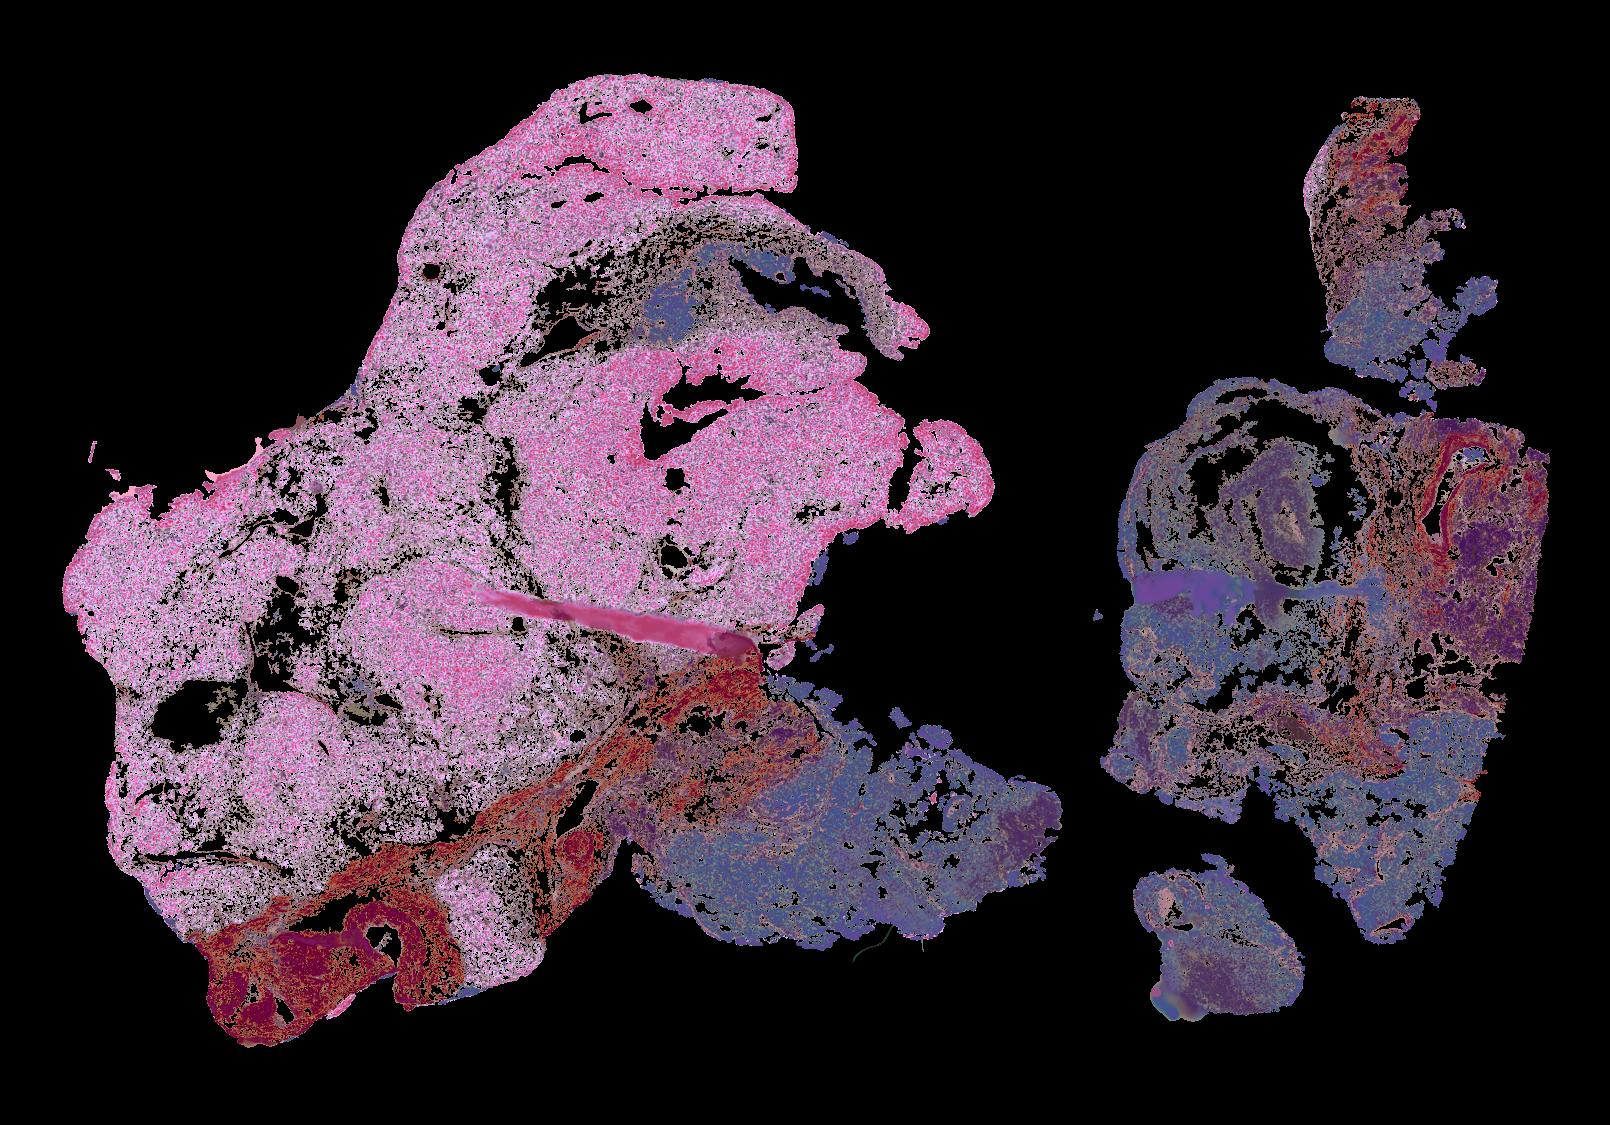

To study the spatial interactions among cancer and non-cancer cells1, we here examined a cohort of 131 tumour sections from 78 cases across 6 cancer types by Visium spatial transcriptomics (ST). This was combined with 48 matched single-nucleus RNA sequencing samples and 22 matched co-detection by indexing (CODEX) samples. To describe tumour structures and habitats, we defined ‘tumour microregions’ as spatially distinct cancer cell clusters separated by stromal components. They varied in size and density among cancer types, with the largest microregions observed in metastatic samples. We further grouped microregions with shared genetic alterations into ‘spatial subclones’. Thirty five tumour sections exhibited subclonal structures. Spatial subclones with distinct copy number variations and mutations displayed differential oncogenic activities. We identified increased metabolic activity at the centre and increased antigen presentation along the leading edges of microregions. We also observed variable T cell infiltrations within microregions and macrophages predominantly residing at tumour boundaries. We reconstructed 3D tumour structures by co-registering 48 serial ST sections from 16 samples, which provided insights into the spatial organization and heterogeneity of tumours. Additionally, using an unsupervised deep-learning algorithm and integrating ST and CODEX data, we identified both immune hot and cold neighbourhoods and enhanced immune exhaustion markers surrounding the 3D subclones. These findings contribute to the understanding of spatial tumour evolution through interactions with the local microenvironment in 2D and 3D space, providing valuable insights into tumour biology.